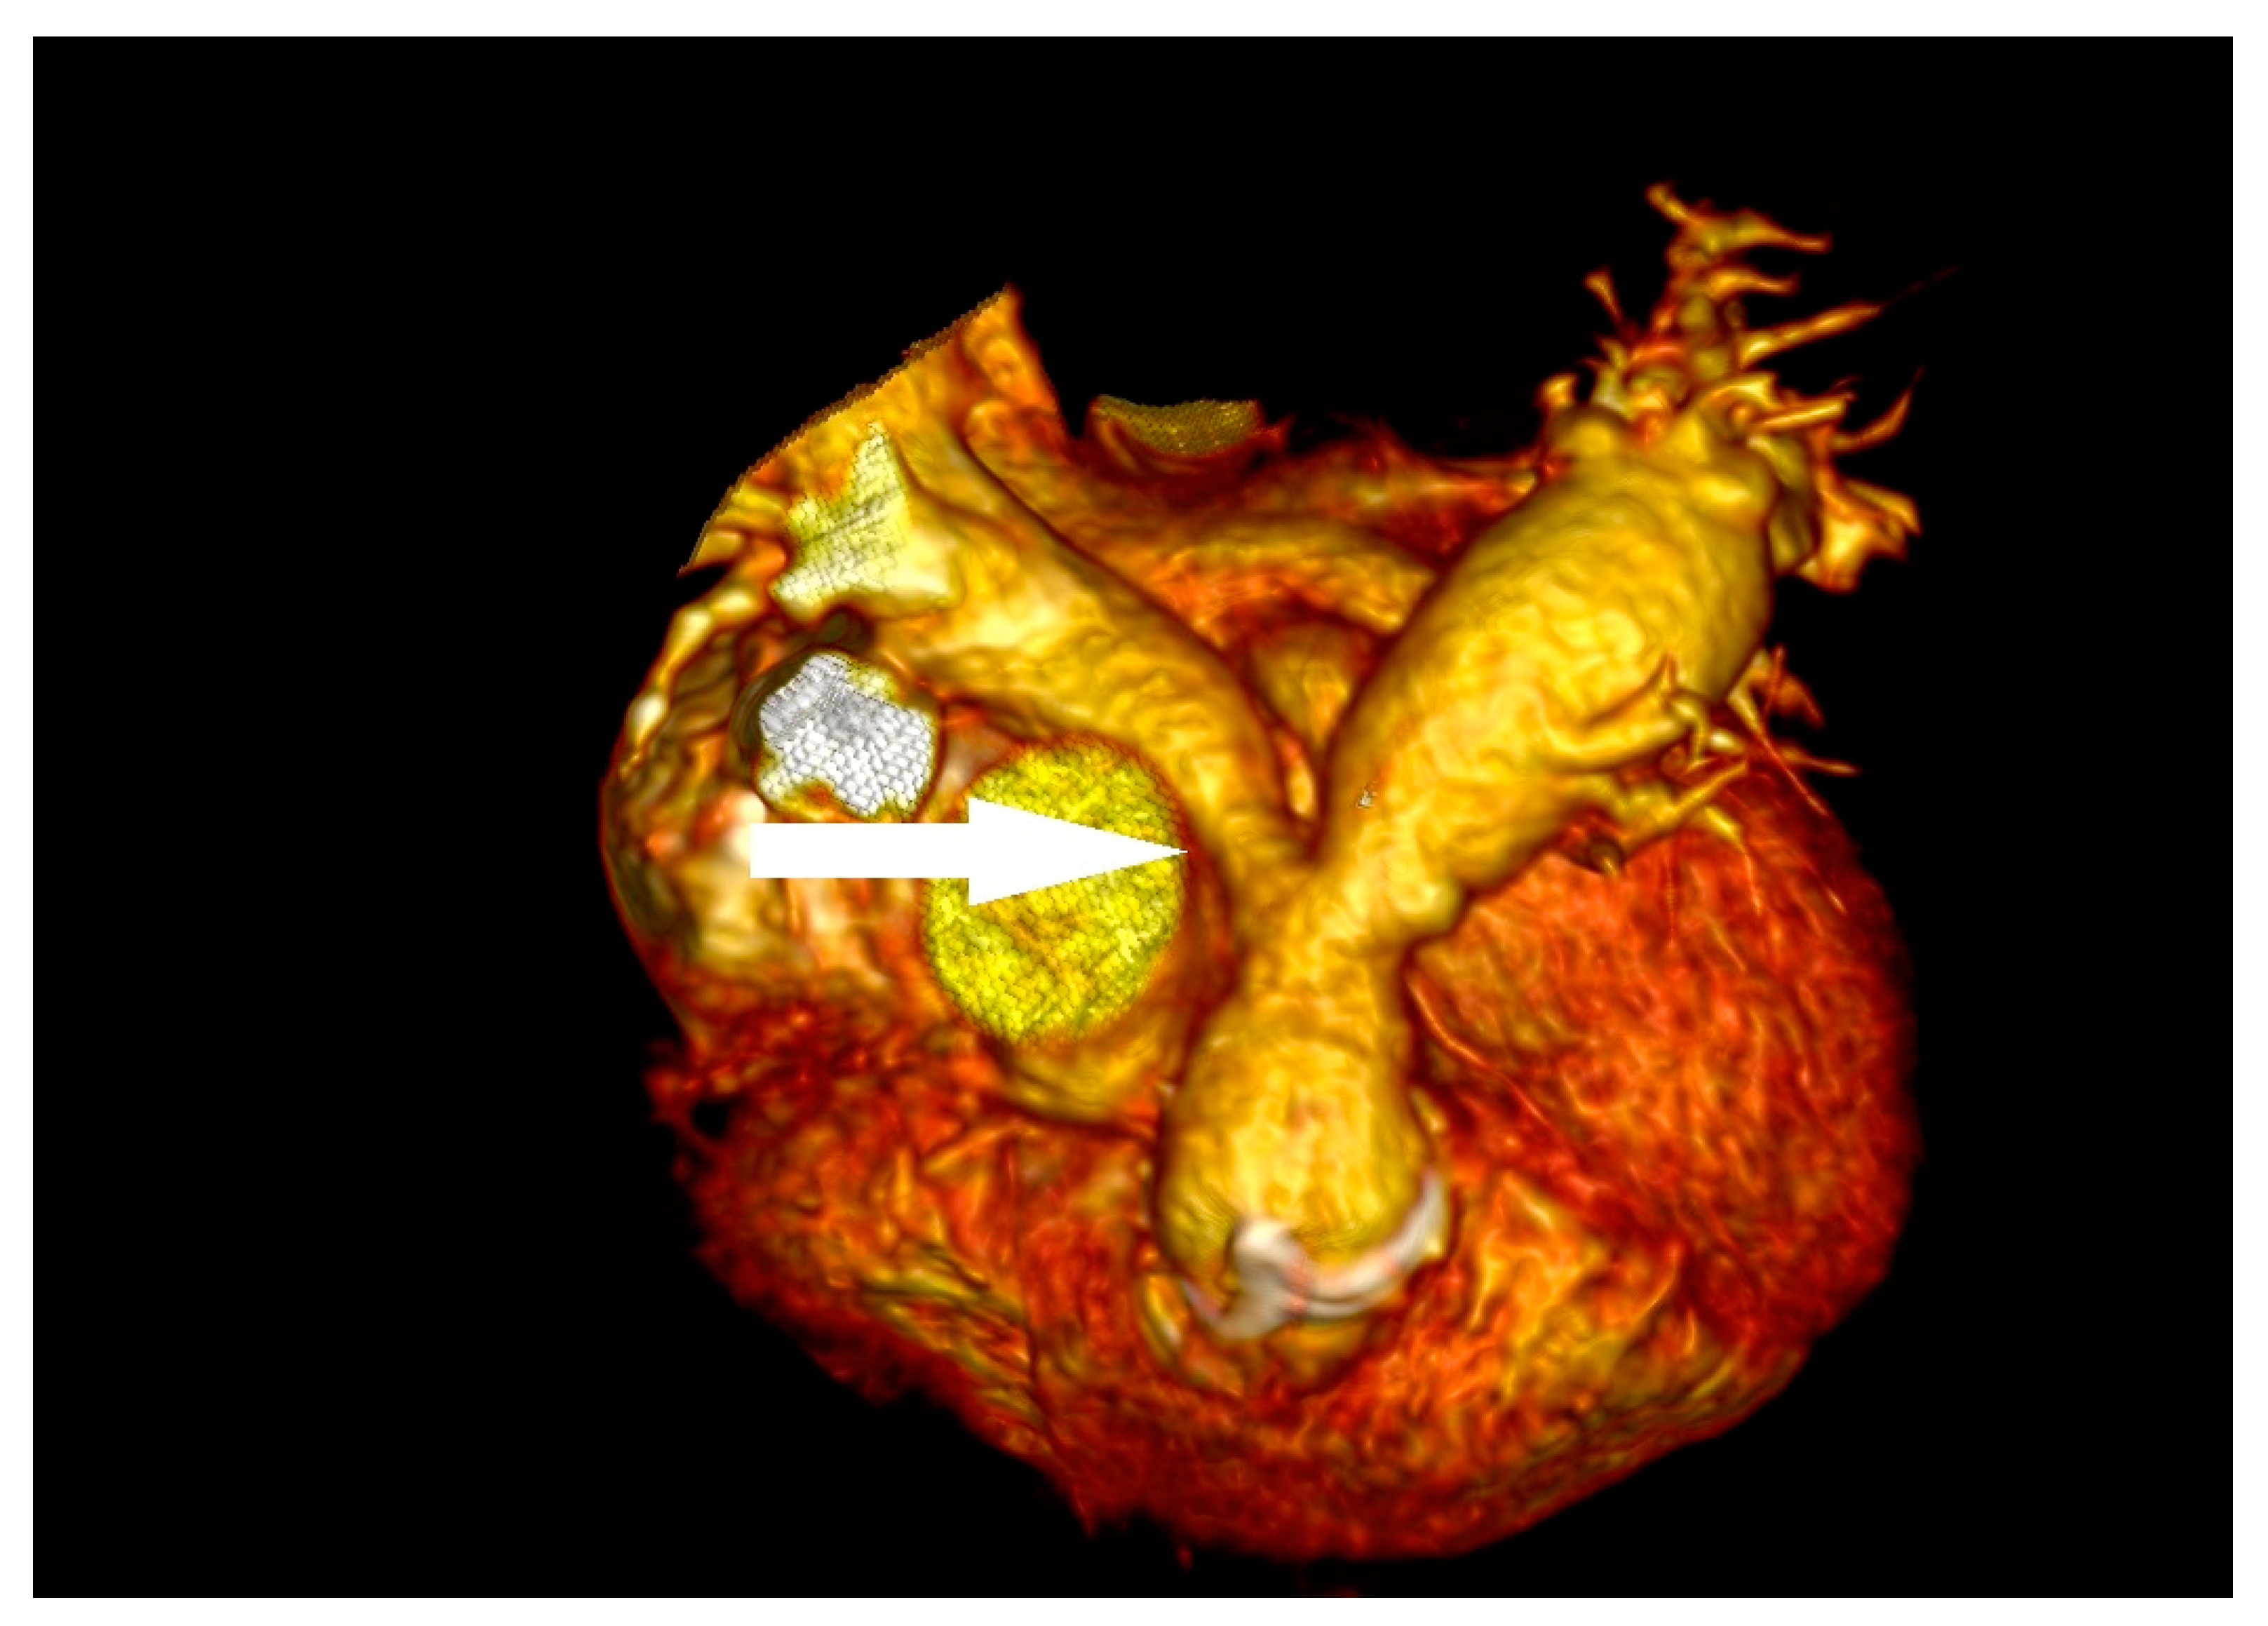

3.4. Case 4